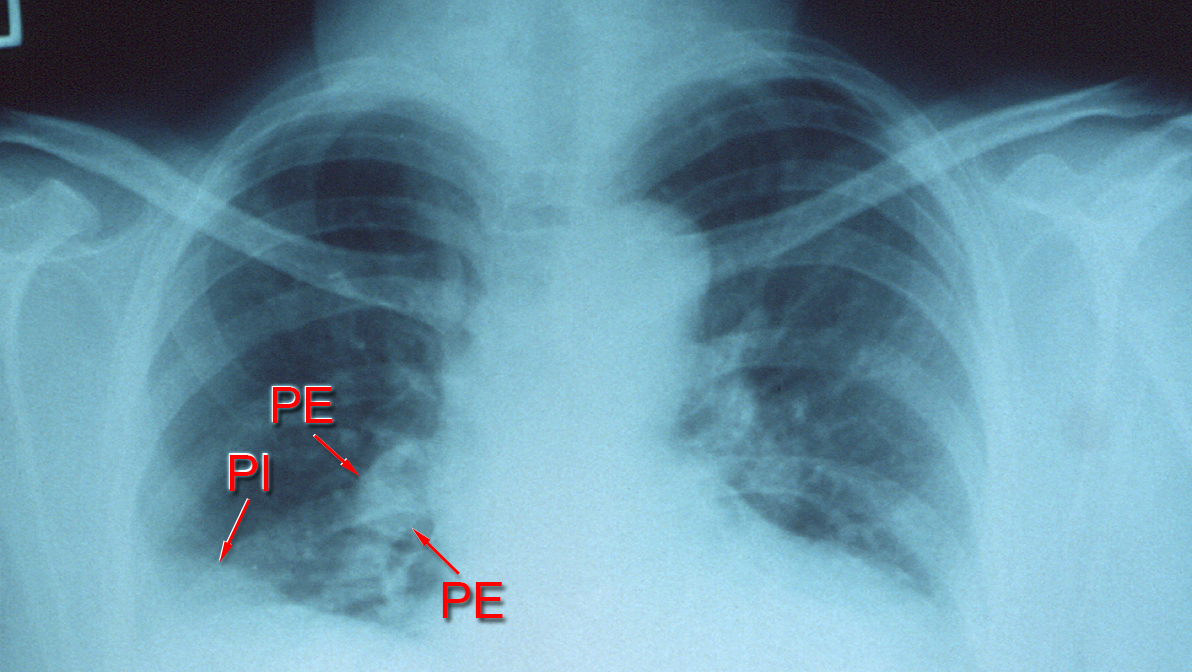

Over the last 20 years, treatments for pulmonary embolism advanced greatly. Several new therapies were developed alongside widespread adoption of emergency response teams for the condition, which is marked by a blockage of the arteries in the lungs often caused by a blood clot.

Researchers analyzed over 100,000 deaths related to pulmonary embolism between 2006 and 2019 using national data from the Centers for Disease Control and Prevention.